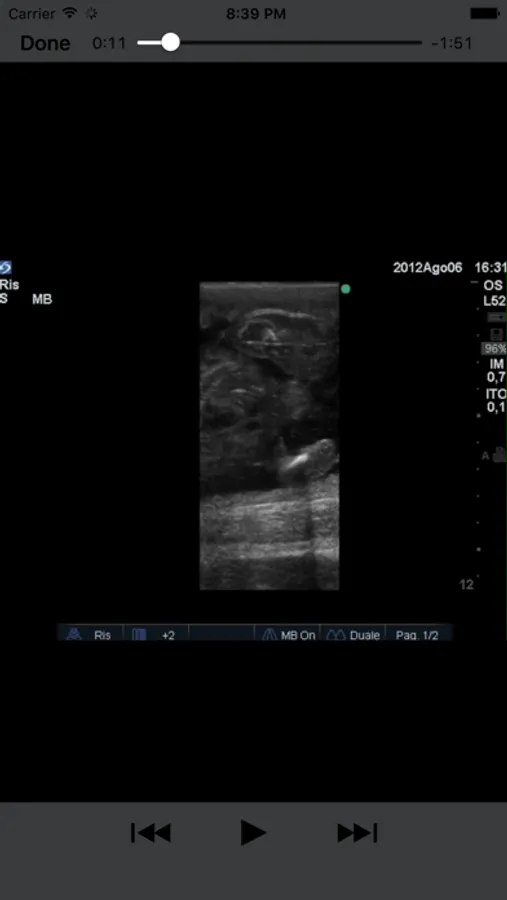

Comprehensive notes are included for each condition with multiple still images. Fetal sexing is described and carefully illustrated in multiple planes for each stage of gestation. The still pictures demonstrate the classic appearance of each stage and are labeled where necessary. The video loops simulate the real life situation and allow the user to test their observational skills on moving images. This is an invaluable tool for continuing professional education of any veterinarian interested in stud work.